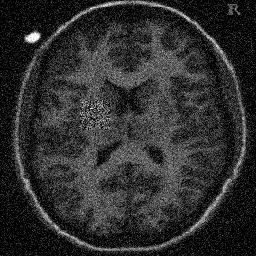

4.1. Uniform Gaussian noise

In this first experiment, we consider the denoising problem with brain scan images. The first set consists of images of pixels and Gaussian noise with zero mean and variance . The original and noisy images are shown in Figure 4.1. The domain decomposition-semismooth Newton algorithms run with the parameter values , , and . The results are shown in Figure 4.2. From the surface representation of , we can observe that is continuous and its shape is related to the one of the original image. In particular, the regularization is stronger in homogeneous regions in the image, and weaker where the image intensity undergoes variations on a smaller scale.

In Table 4.1 the performance of the different methods is compared. For all of them, only the first 2 domain decomposition iterations were considered. The total number of SSN iterations differ at most by one. The impact of the domain decomposition method becomes clear when comparing the computing times of the methods, corresponding to one, two and four subdomains. The computing time is significantly reduced. The effect of the optimized transmission conditions can be realized when comparing the gap between subdomains, which is much lower in the case of optimized transmission conditions () than in the standard Schwarz method ().